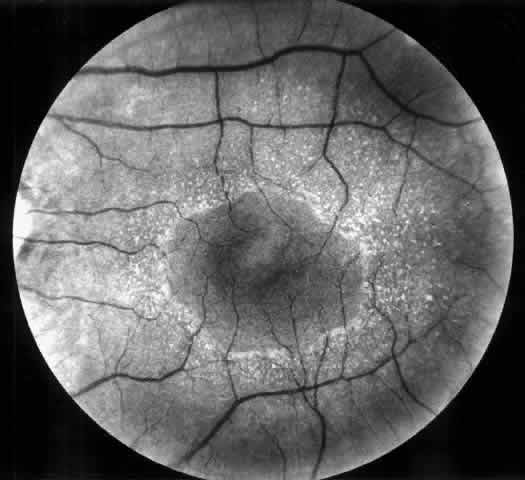

Arterial hypertension is a frequent complication of congenital and acquired renal and renovascular disorders. Arteriolar narrowing, tortuosity, and arteriovenous nicking are common retinal vascular abnormalities in patients with arterial hypertension. In subjects with malignant hypertension, ischemic changes may occur in retina, choroid, and optic nerve and produce cotton-wool spots, flame-shaped hemorrhages, hard exudates, Elschnig's spots, exudative detachment, papilledema, and optic atrophy (Fig. 1). In patients with severe and long-standing hypertension a sudden relative fall in arterial pressure may cause infarction of the optic nerve and blindness. Anterior ischemic optic neuropathy and retinal infarction have been described as complications of hemodialysis-associated hypotension. Uremia, anemia, and papilledema of intracranial hypertension are other risk factors for optic neuropathy in patients with chronic renal diseases.2 In addition, patients with chronic hypertension are predisposed to retinal arterial and venous obstructive diseases leading to visual loss.

Fig. 1. Malignant hypertension with retinal and choroidal vascular manifestations: retinal hemorrhages, exudative retinal detachment, numerous edematous Elschnig's spots (A), and fluorescein angiographic abnormalities with areas of hypoperfusion of the choriocapillaris in the early phase (B), and diffuse leak of fluorescein in the late phase of angiography (C).